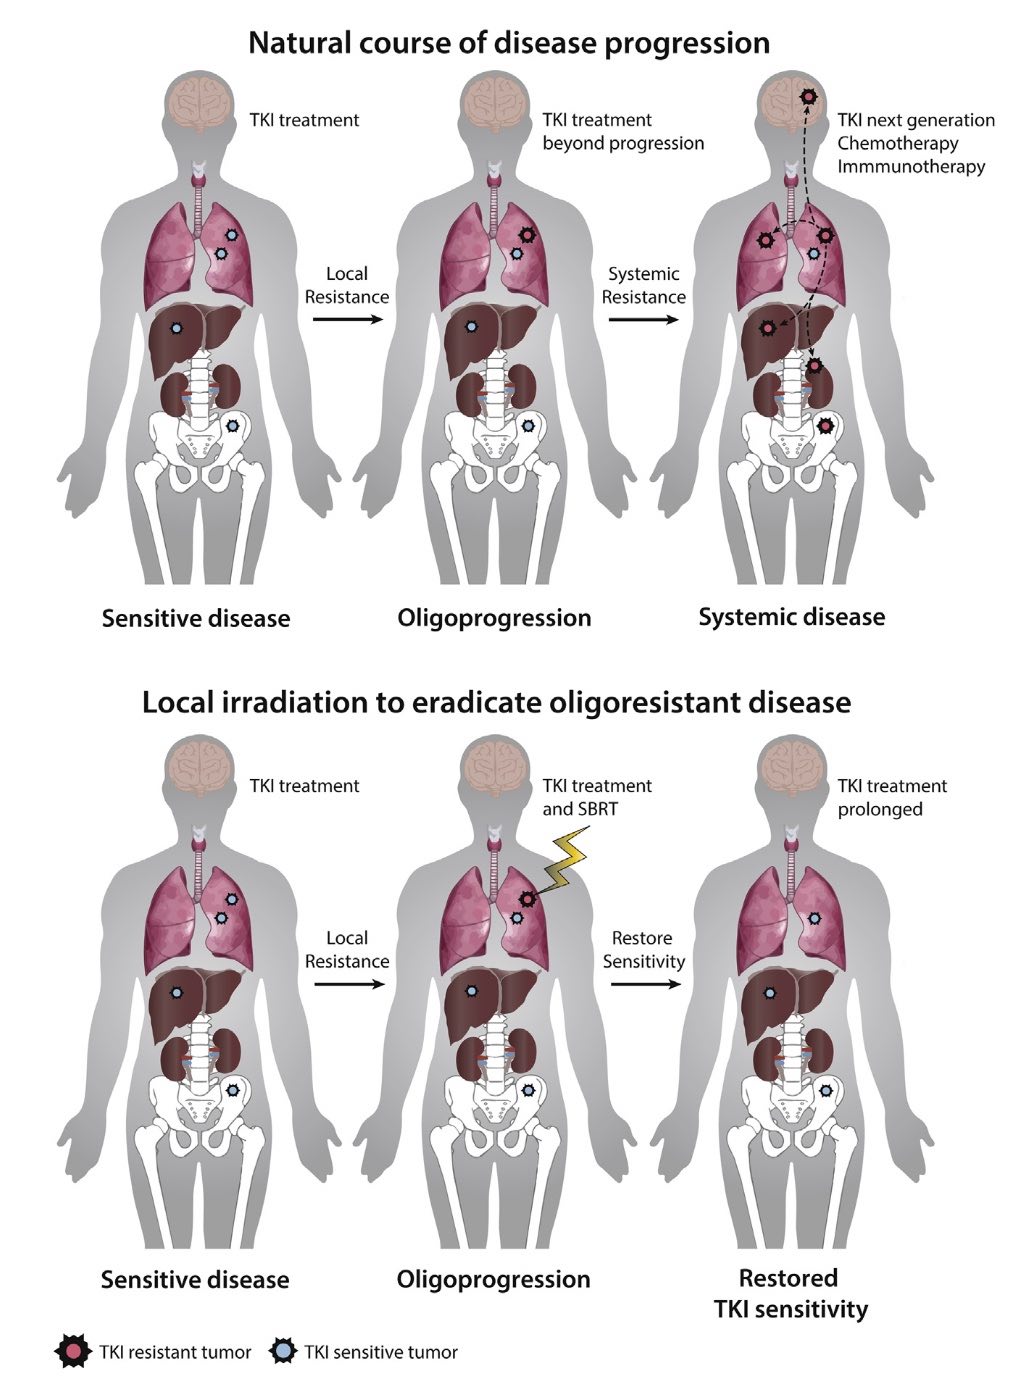

SBRT for oligoprogressive oncogene addicted NSCLC

Lung cancer is one of the leading causes of cancer death in men and women and treatment outcome continues to lag behind other common cancer types. A subset of lung adenocarcinoma patients exhibit a somatic mutation in EGFR or an ALK rearrangement. In these patients, targeted TKI therapy results in higher response rates, improved PFS and reduced side effects compared with platinum-based chemotherapy.

Despite initial activity of the TKIs, ultimately all patients present with disease progression after about a year on TKI therapy due to resistance development. About 15-47% of patients present with limited oligoprogressive disease (OPD): such patients show only a limited number of metastases with progression in radiological imaging. Radical local treatment to all oligoprogressive lesions is thought to eradicate the de-differentiated clones and restore overall sensitivity of the metastatic disease. Retrospective studies suggest that aggressive local treatment using stereotactic body radiotherapy (SBRT), surgery or others can be used to eradicate TKI-resistant subpopulations enabling prolonged TKI treatment "beyond progression", which may lead to increased PFS and overall survival.

This review focuses on the biological background of resistance development, systemic and local treatment options with a focus on SBRT, as well as challenges in defining the state of OPD and current clinical studies in oligoprogressive oncogene addicted NSCLC.